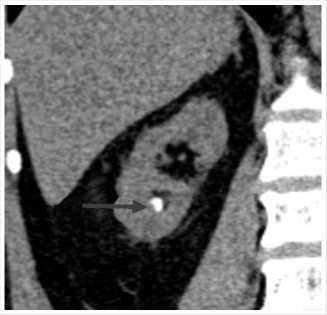

Рис. 3. МСКТ в нативном режиме, сделанная в июне 2023 г. Отмечен полный литолиз крупного камня ЛМС справа.

Повторно обратилась за медицинской помощью, консультирована урологом НМХЦ им. Н.И. Пирогова, повторно предложено проведение оперативного вмешательства, от которого пациентка вновь решила воздержаться. Пациентке начата литолитическая терапия с целью возможного растворения камней ВМП путем коррекции кислотно-щелочного баланса мочи. Учитывая низкую ком-плаентность, крайне важно объяснить значимость непрерывного приема препаратов по чётко расписанной схеме лечения и постоянного динамического контроля показателей суточного анализа мочи с целью оценки pH мочи и степени урикемии. Литолитическая терапия проводилась с помощью цитрантых смеси. В течение последующего месяца пациентка стала отмечать постепенное купирование болевого синдрома, при контрольной КТ органов мочевыделительной системы, выполненной в августе 2023 г. (на 2-й месяц проводимой терапии) отмечено: ЧЛС обеих почек не расширена (ранее каликопиелоуретероэктазия справа). В нижней группе чашечек правой почки определяются два конкремента, размерами 2,3 x 1,8 мм и 2,4 x 2,6 мм, плотностью до +268 HU (ранее визуализировались не менее 3х конкрементов до 4 мм). В лоханке правой почки конкременты не выявлены (ранее конкремент размерами до 15 x 9,5 мм.) Мочеточник справа при нативном исследовании без значимого расширения, конкрементов в нем достоверно определяется. Выявляемые ранее уплотнение клетчатки на уровне лоханочно-мочеточникового перехода справа и увеличенный парааортальный лимфоузел справа–при настоящем исследовании не определяются. Конкременты левой почки не выявлены. Выявляемый ранее конкремент в области лоханочно-мочеточникового перехода

Рис. 4. МСКТ в нативном режиме, сделанная в июне 2023 г. Отмечено уменьшение камней нижней группы чашечек правой почки.

Рис. 5. МСКТ в нативном режиме, сделанная в июне 2023 г. Стрелкой указан конкремент нижней трети левого мочеточника, мигрировавший из области ЛМС.

слева, размерами до 4,8 x 3,5 мм, плотностью до +452 HU–при исследовании выявлен в нижней трети левого мочеточника. Левый мочеточник не расширен (Рис. 3–5).